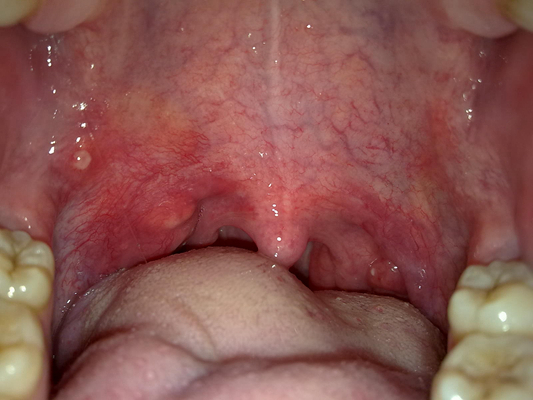

扁桃體週膿腫圖片